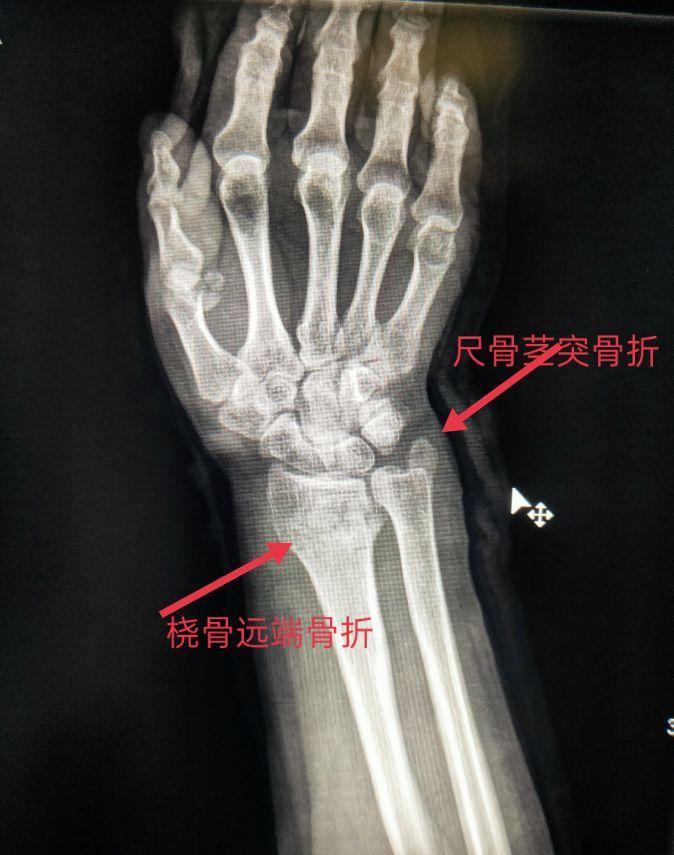

尺骨为前臂的稳定骨,是两根前臂骨中位于内侧且较长的骨,分二端一体。尺骨上端膨大,其上突的鹰嘴呈不整的四方形。它与肱骨滑车下缘相对应,构成肱尺关节。尺骨下端的是尺骨小头和尺骨茎突。尺骨小头与桡骨的尺骨切迹相对应,构成桡尺远侧关节。

桡骨位于前臂外侧部,分一体两端。上端膨大称桡骨头,头下方略细,称桡骨颈,颈的内下侧有突起的桡骨粗隆。桡骨下端前凹后凸,外侧向下突出,称茎突。桡骨茎突和桡骨头在体表可扪到。

在尺、桡骨正位片上可以看到尺骨、桡骨、肘关节(部分肱骨、鹰嘴窝、肱骨滑车、肱骨外上髁、肱骨内上髁)、腕关节(手舟骨、月骨、三角骨、豆状骨、大多角骨、小多角骨、头状骨、钩状骨、部分掌骨)。

四、尺、桡骨骨折X线片

尺骨桡骨骨折以桡骨远端骨折多见。其次是尺骨桡骨双骨折,多发生于青少年。